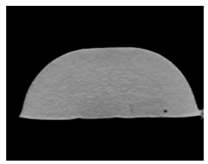

| MRI–T2 |  |  |  |

| MRI–T2 |  |  |  |

| MRI–T2 |  |  |  |

| MRI–T2 |  |  |  |

| MRI–T2 |  |  |  |

| MRI–T2 |  |  |  |